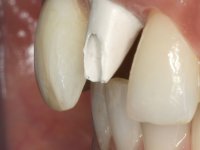

O ajuste final da cor/shade da restauração directamente em boca têm grande importância no sucesso do tratamento. Qualquer alteração necessária pode ser realizada nesta fase. As tonalidades de dentina e incisais foram aplicadas em conjunto de acordo com o esquema de estratificação visando a sua caracterização individualizada, mas ainda não foi aplicada a camada de superfície que dá translucidez á restauração. Este facto, permite que possíveis deficiências na cor/shade possam ser corrigidas removendo porções de cerâmica que apresentem tonalidades indesejadas. O brilho/brightness da primeira camada não deve ser muito baixo, porque pode fazer com que a restauração apresente um aspecto acinzentado. Esta situação pode ser contornada utilizando uma pastilha um pouco mais clara do que a cor/shade que se pretende para o resultado final.

Neste caso a paciente foi vista no laboratório, o que tornou possível estabelecer o correcto nível de saturação da cor e brilho. Quando a construção da cerâmica estava optimamente ajustada em termos de cor/shade, os componentes da translucidez puderam ser finalmente acrescentados. Nesta fase foi também completada a anatomia e a textura superficial de acordo com a informação dada pelos detalhes reproduzidos no modelo. A caracterização com tonalidades e essências no ciclo final de cozedura é fundamental, permitindo um ajuste fino da caracterização.

A confecção de um coto de óxido de zircónio com uma coroa de cerâmica vítrea prensada de dissilicato de lítio mimetizou perfeitamente os dentes vizinhos.